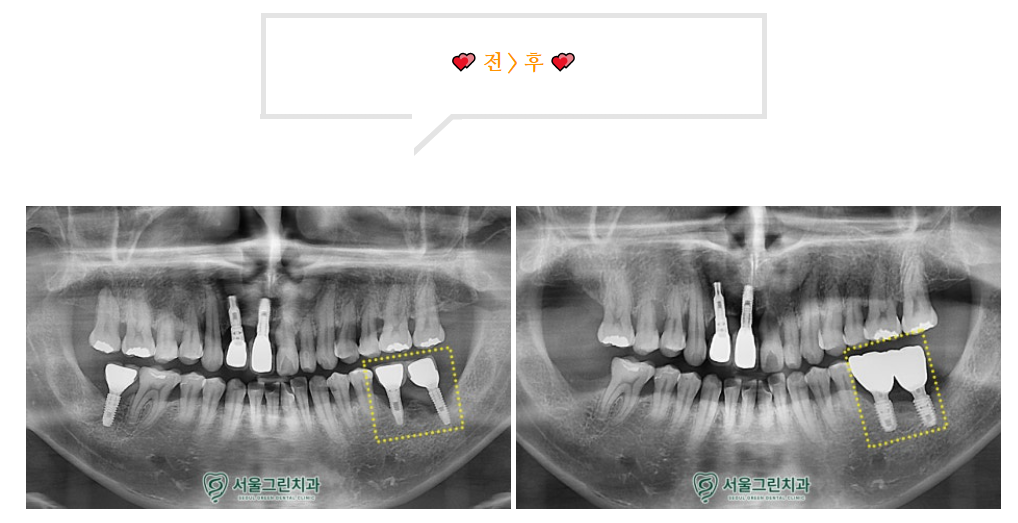

파노라마상에서

식립되어있는 임플란트 주변으로

잇몸뼈가 많이 녹아

까맣게 비춰보이는 모습을

확인할 수 있었습니다.

잇몸뼈에 잘 고정된것을 확인하고,

크라운(보철물)까지

안정적으로 셋팅해드린 모습입니다!